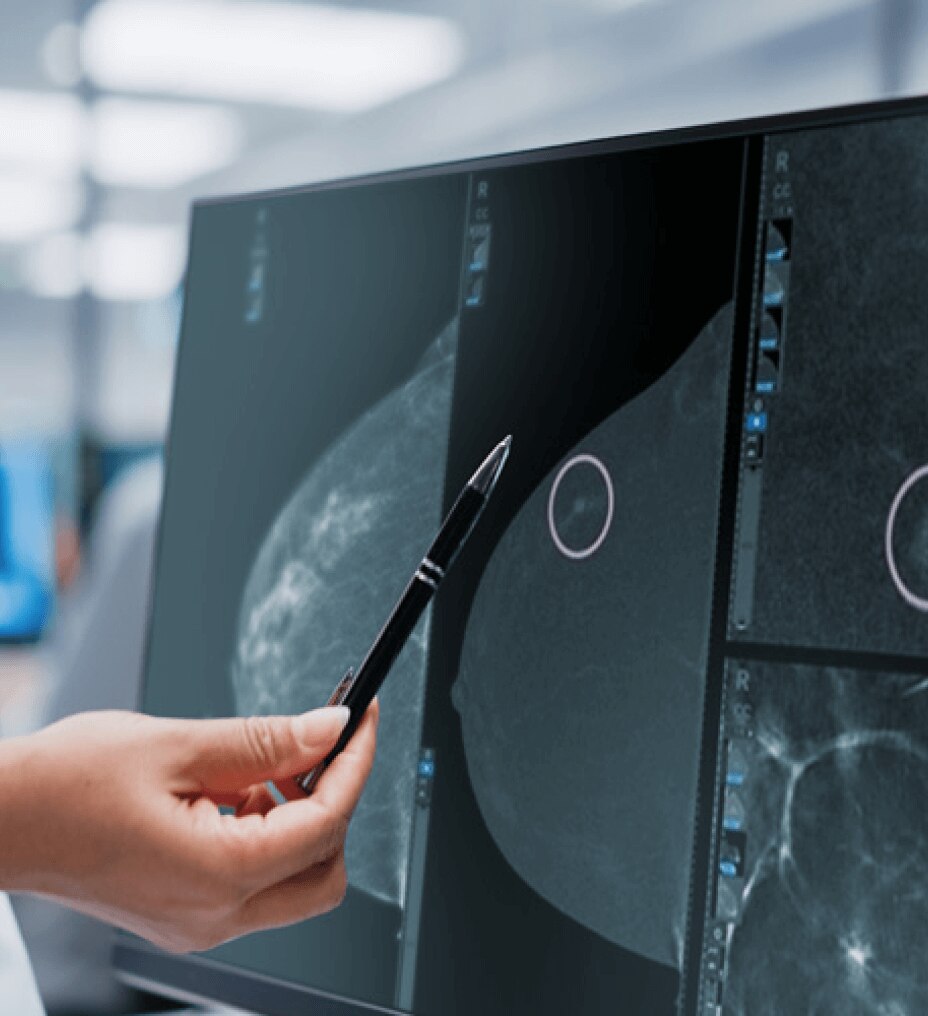

Elevata qualità delle immagini

Grazie alla tecnologia di Deep Learning AIR Recon DL puoi ottenere immagini nitide in tempi rapidi.